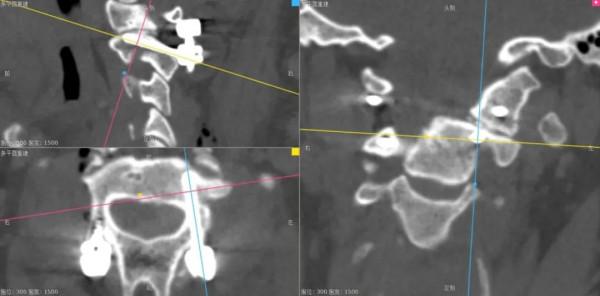

- 面對椎動脈高跨,“小心假設,大膽求證”,總能找到合適的釘道。

- 本例選擇靠近C1-2小關節的上關節面和靠近C2峽部內側的位置建立釘道。